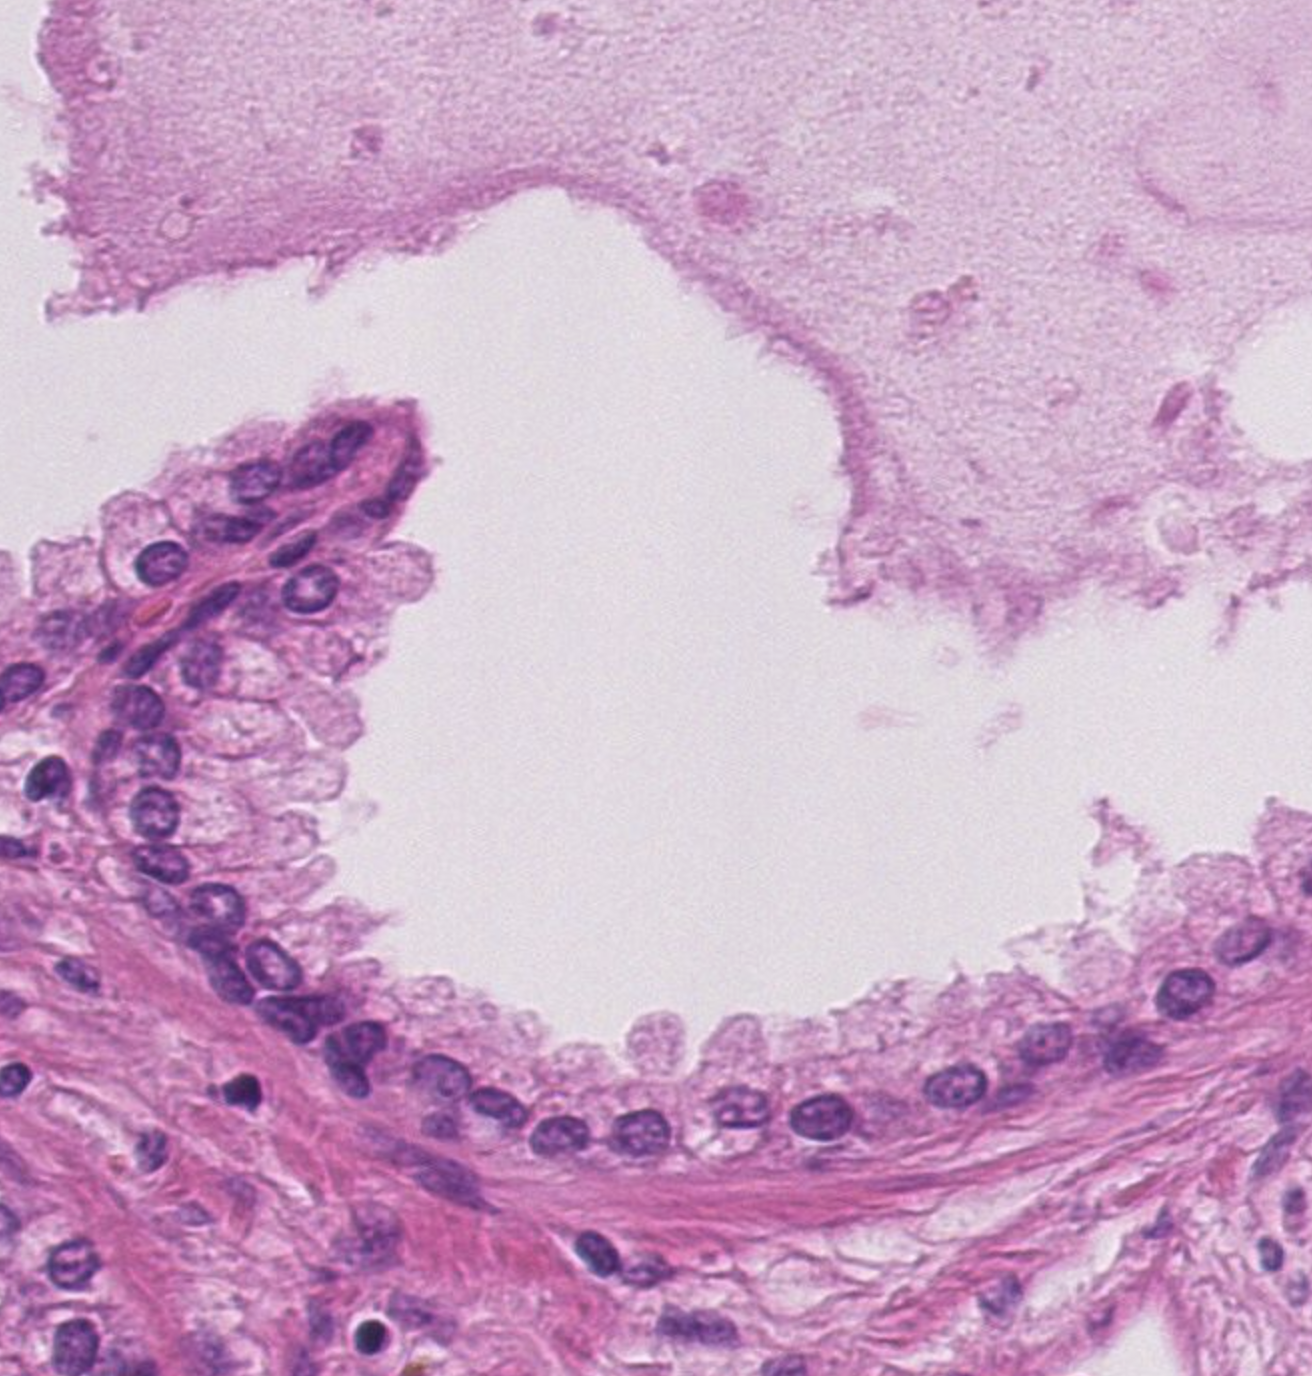

41) Z698 Pankreatitis - Beschreiben Sie die histopathologischen Merkmale.

Zu sehen ist eine Pankreatitis. Hier soll es um besonders um die Fettegwebsnekrose gehen. Eine Lipolytische Fettgewebsnekrose, der Pankreas verdaut sich quasi selber, denn bei der Entzündung des Pankreas werden die Pankreasenzyme die sonst in den Dünndarm geleitet werden

Hier betrifft die Nekrose erstmal nur die Fettzellen, würde aber auch auf das Paarenchym übergehen. Es zeigt sich außerdem Lymphozytäres infiltrat im sinne von neutrophilen Granulaten Histopathologisches Bild: Prostatahyperplasie mit knotiger Architektur Trypsinische Parenchymnekrose Das aktivierte Trypsin führt zur Proteolyse (Eiweißspaltung) des Pankreasparenchyms (der Drüsenzellen, Gefäßwände usw.). Diese Zerstörung des Pankreasgewebes nennt man tryptische Parenchymnekrose. Histopathologisches Bild: Prostatahyperplasie mit knotiger Architektur